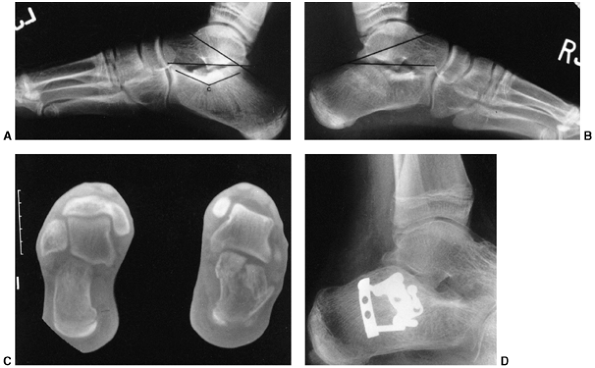

an oblique growth arrest line (41) (Fig. 33.3). Magnetic resonance imaging (MRI) may also be useful to detect early physeal arrest (42,43).

The most common type is a peripheral bar, which produces an angular

deformity. The second type is a central bar, which acts as a central

tether and results in tenting of the physis with eventual articular

surface distortion. The third pattern of bar formation is referred to

as a linear bar and involves portions of

the central and peripheral physis. This last type is often the result

of a Salter-Harris type IV fracture that has healed in a displaced

position.

Before surgical excision, it is necessary to clearly delineate the

extent and location of the bar. Plain radiography should be performed

with the beam centered on the growth plate and tilted in the same plane

as the growth plate. Helical computed tomographic scanning and MRI have

largely replaced traditional tomography (49). Three-dimensional reconstruction using these techniques allows accurate identification of the size and location of the bar (50).

![]() |

|

Figure 33.5 Physeal bar resection. A: A distal physeal bar is depicted in this anteroposterior hypocycloidal tomogram. B:

This condition was treated with bar excision and insertion of Cranioplast. Five months later, the physis remains open, and the two metal markers inserted at the time of surgery are 28 mm apart. There is residual femoral tibial valgus deformity. C: Four years later, there has been some improvement in the femoral tibial alignment, and growth of the distal femur has resumed. The markers are 83 mm apart. |